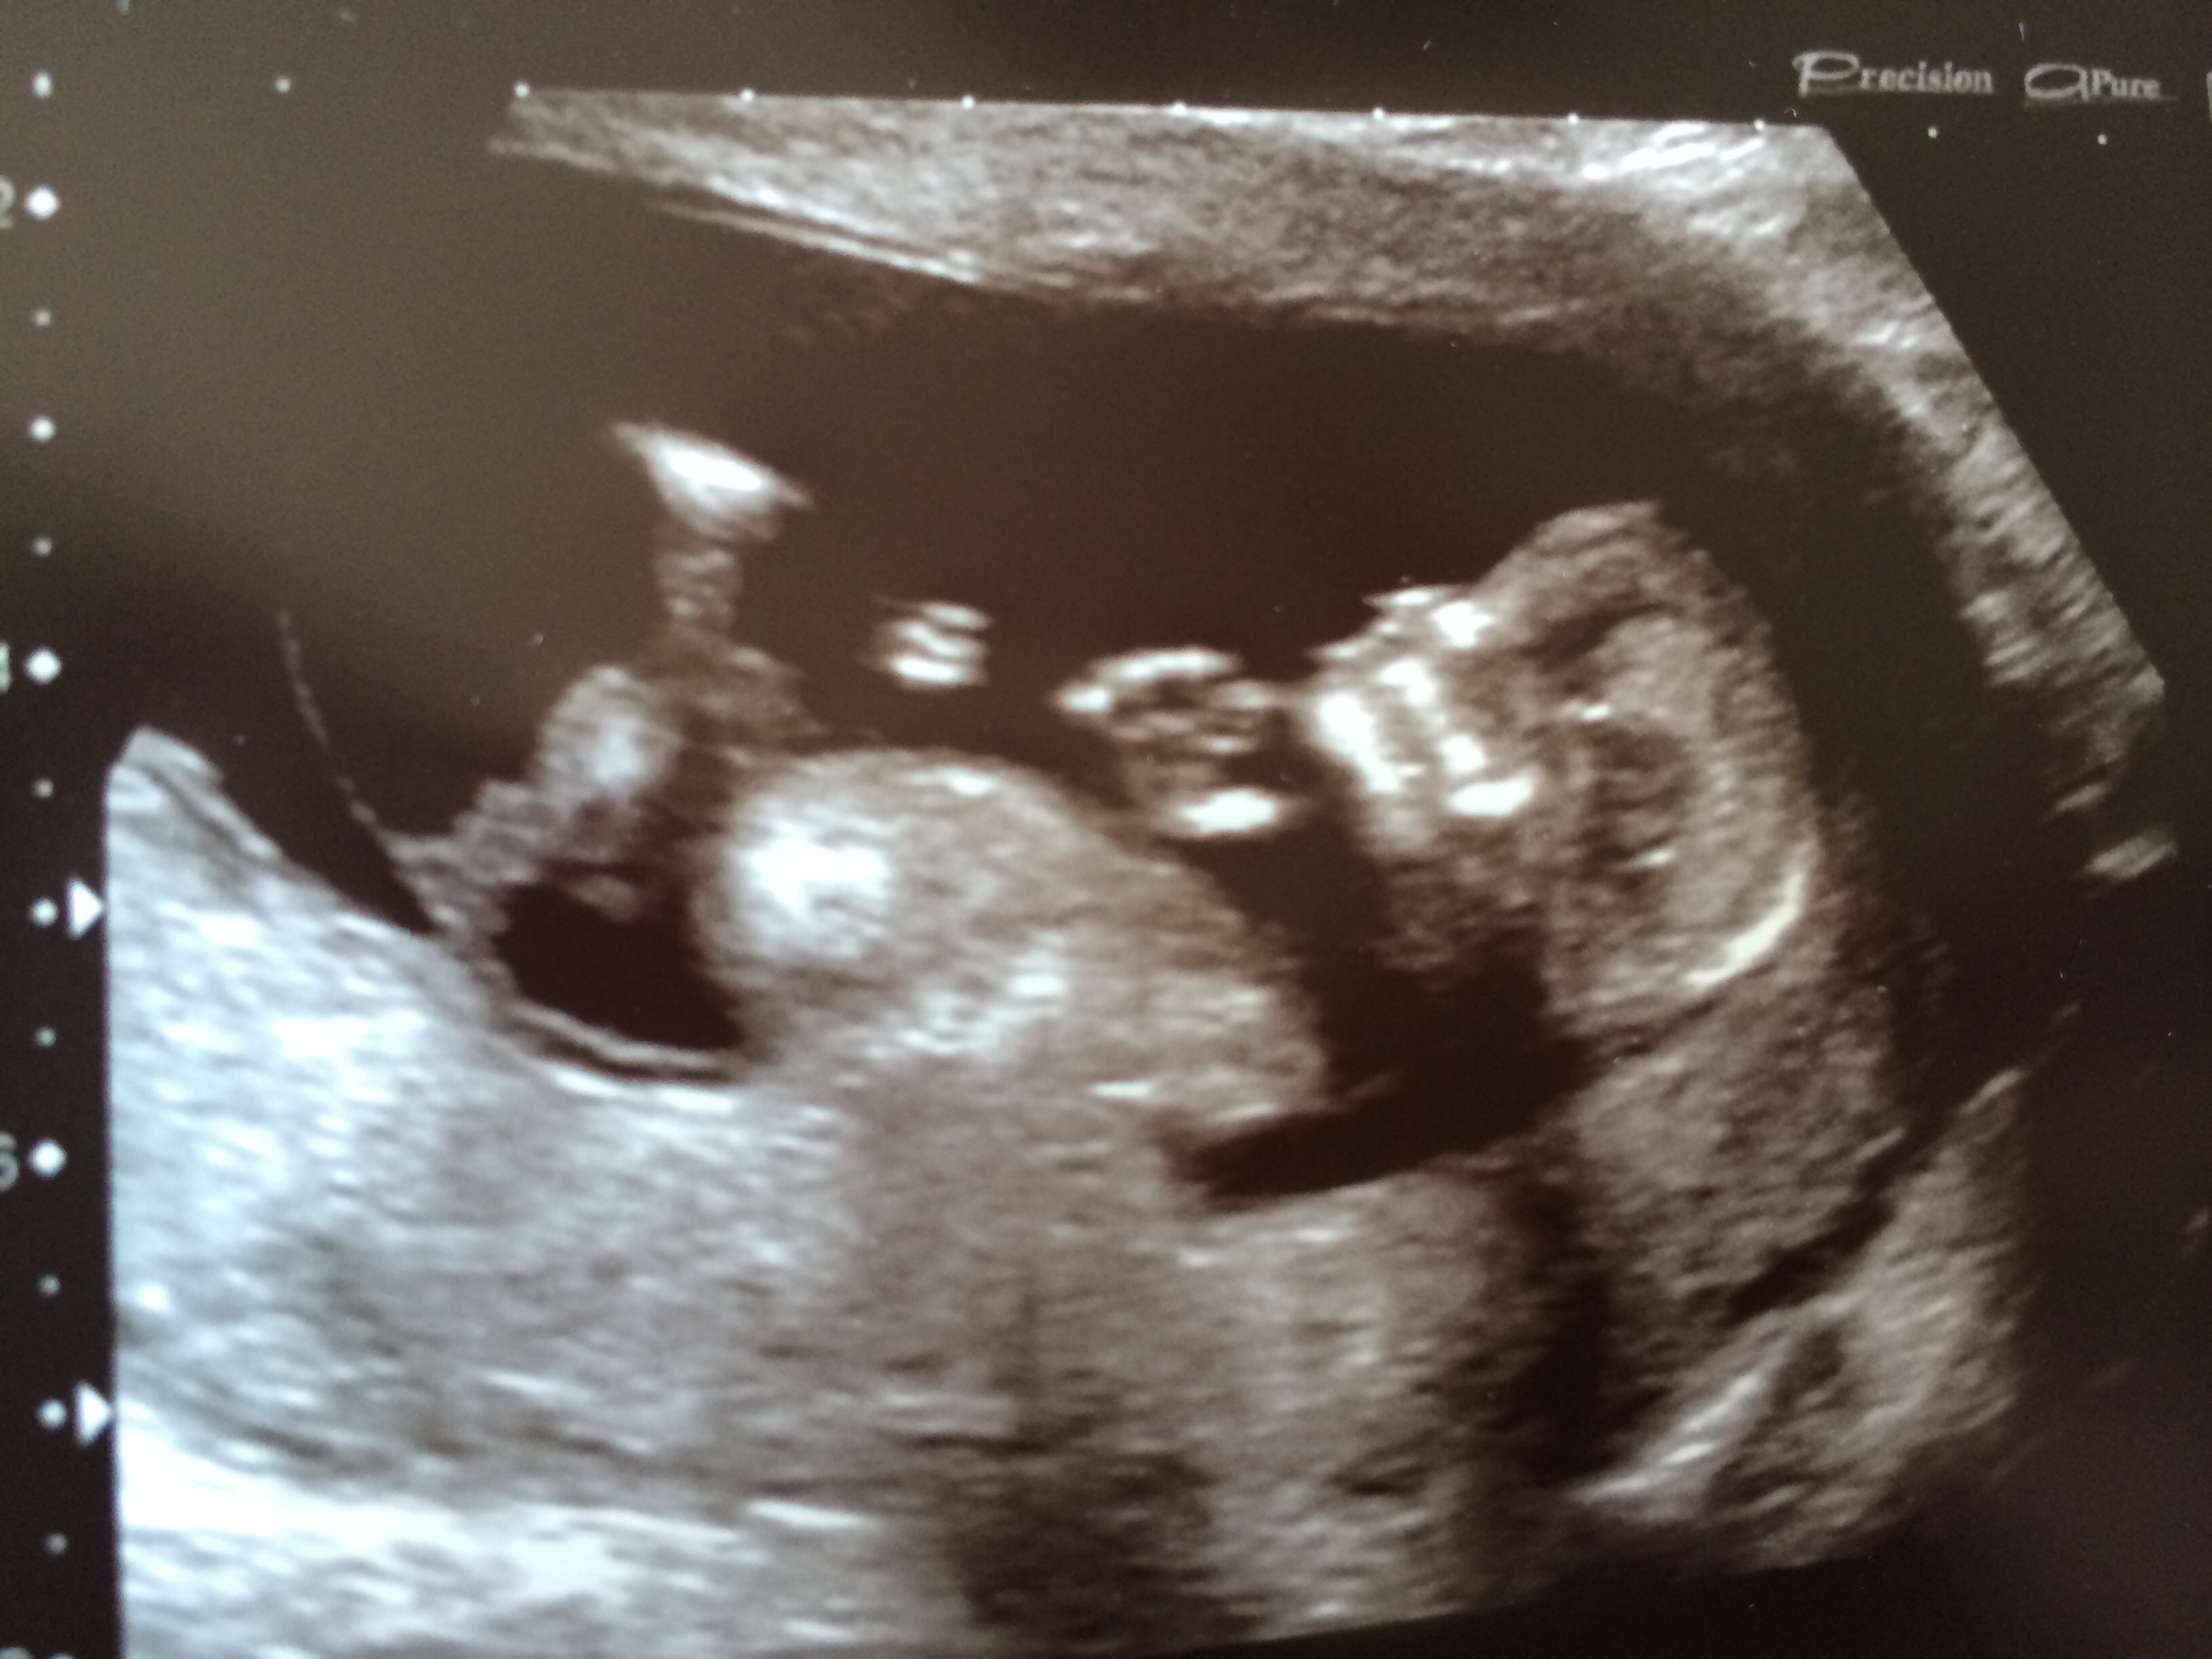

First pic is at 7+6, second two are today at 12+5 - don't think I see a nub, but any guesses are very welcome!! TIA ladies :)

I (Personally) don't see a nub, but what a cute baby! Good Luck!

No nub, but beautiful baby!!